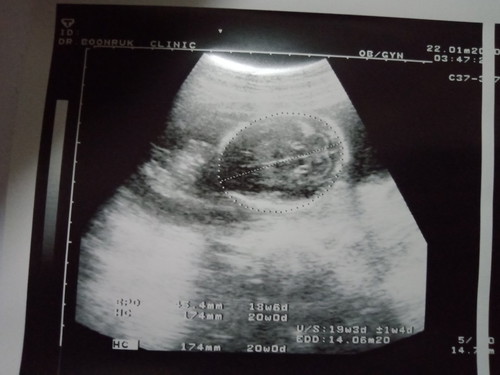

5เดือนแล้วคะ

แม่ๆว่าแบบนี้เพศไหนคะ

นี่ภาพกระโหลกจ๊ะ ไม่บอกเพศ ถ้าบอกเพศ ต้องภาพมุมหว่างขาค่ะ